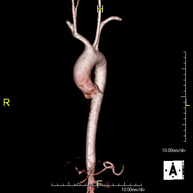

- Supra-aortic trunk MRI angiography

This non-invasive diagnostic procedure uses an electromagnetic field and radio waves (from a transmitter and receiver) to acquire high-definition anatomical images of the carotid and vertebral arteries in the neck. It is a radiation-free procedure. In most cases, paramagnetic contrast (gadolinium) is required. It enables non-invasive angiographic studies using a gadolinium injection, with subsequent 2D and 3D reconstruction using specialised workstations. Indicated for: Cerebral circulatory problems, syncope.

- Thoracic aorta MRI angiography

This non-invasive diagnostic procedure uses an electromagnetic field and radio waves (from a transmitter and receiver) to acquire high-definition anatomical images of the thoracic aorta. It is a radiation-free procedure. In most cases, paramagnetic contrast (gadolinium) is required. It enables non-invasive angiographic studies using a gadolinium injection, with subsequent 2D and 3D reconstruction using specialised workstations. It also includes an aortic valve examination, which is essential information if the patient needs surgery. This test is especially indicated in patients requiring surgical processing (such as pre-surgical vascular mapping), in the tracking of patients with aortic aneurysms, etc.